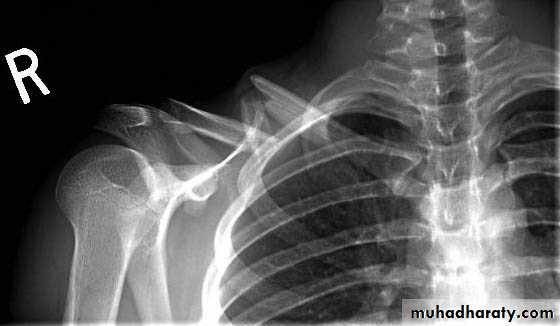

3-The Acromioclavicular joint:

How the AC joint is injured?The AC joint is a quite common sporting injury especially in contact sports. It is usually injured by a fall directly onto the shoulder or a fall onto the arm or a tackle.

The ligaments that bind the clavicle to the acromion are firstly stretched, and thentorn. Depending on the severity of the injury the clavicle can tear away from the acromion causing a noticeable lump to appear on top of the shoulder. The injury results in considerable pain, swelling and loss of shoulder movement.

Grading of an AC joint injury:

The most commonly used classification system recognizes 6 severities of AC joint injury.grade I

A slight displacement of the joint. The acromioclavicular ligament may be stretched or partially torn. This is the most common type of injury to the AC Joint.grade 2

A partial dislocation of the joint in which there may be dome displacement that may not be obvious during a physical examination. The acromioclavicular ligament is completely torn, while the coracoclavicular ligaments remain intact.Grade 3

A complete separation of the joint. The acromioclavicular ligament, the coracoclavicular ligaments and the capsule surrounding the joint are torn. Usually, the displacement is obvious on clinical exam. Without any ligament support, the shoulder falls under the weight of the arm and the clavicle is pushed up, causing a bump on the shoulderGrades I-III are the most common. Grades IV-VI are uncommon and are usually a result of a very high-energy injury such as ones that might occur in a motor vehicle accident.